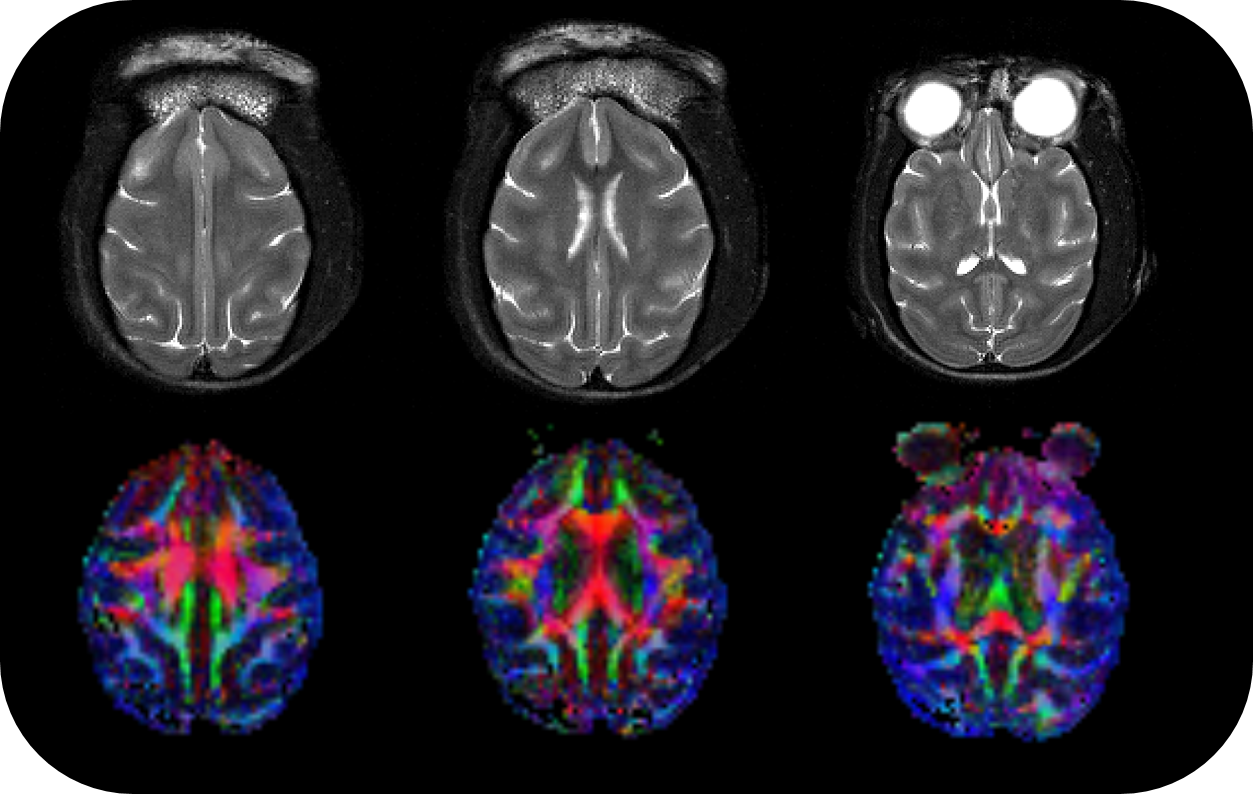

BioSpec 70/30 and 94/30

Studies with intricate set-ups or on animals up to the size of rabbits can be conducted with the extremely physically stable, 30 cm bore size BioSpec 70/30 and BioSpec 94/30.

• Complete RF coil portfolio for mice and rats available, including coils for head, brain, cardiac, body, optogenetics, Arterial Spin Labeling, multi-channel array coils with up to 16 channels, and x-nuclei

• MRI CryoProbes with 2 element, 4 element, or as 13C for mice as well as 4 element for rat delivering an exceptional increase in sensitivity

• MRI sequence portfolio of more than 1,000 sequence variations, including wireless cardiac imaging using navigator based IntraGate methods with cartesian or radial readout, as well as short echo time imaging, such as UTE and ZTE